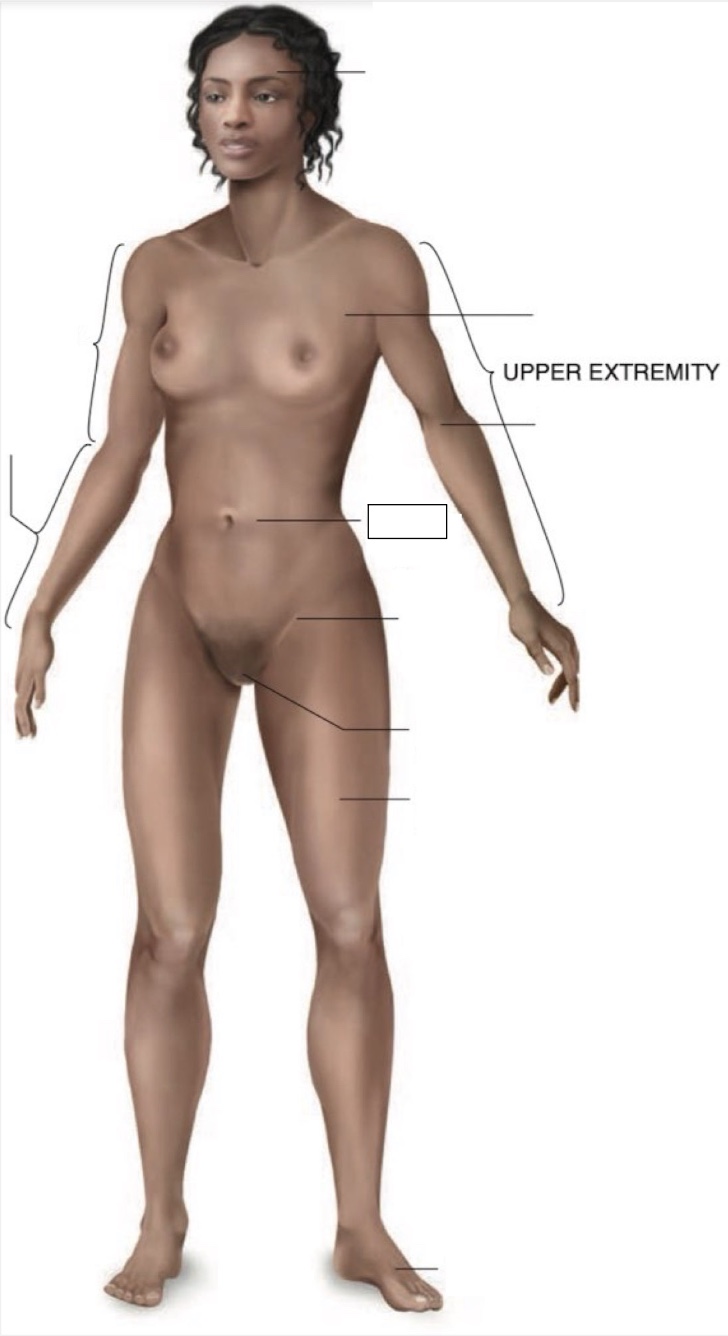

umbilical region